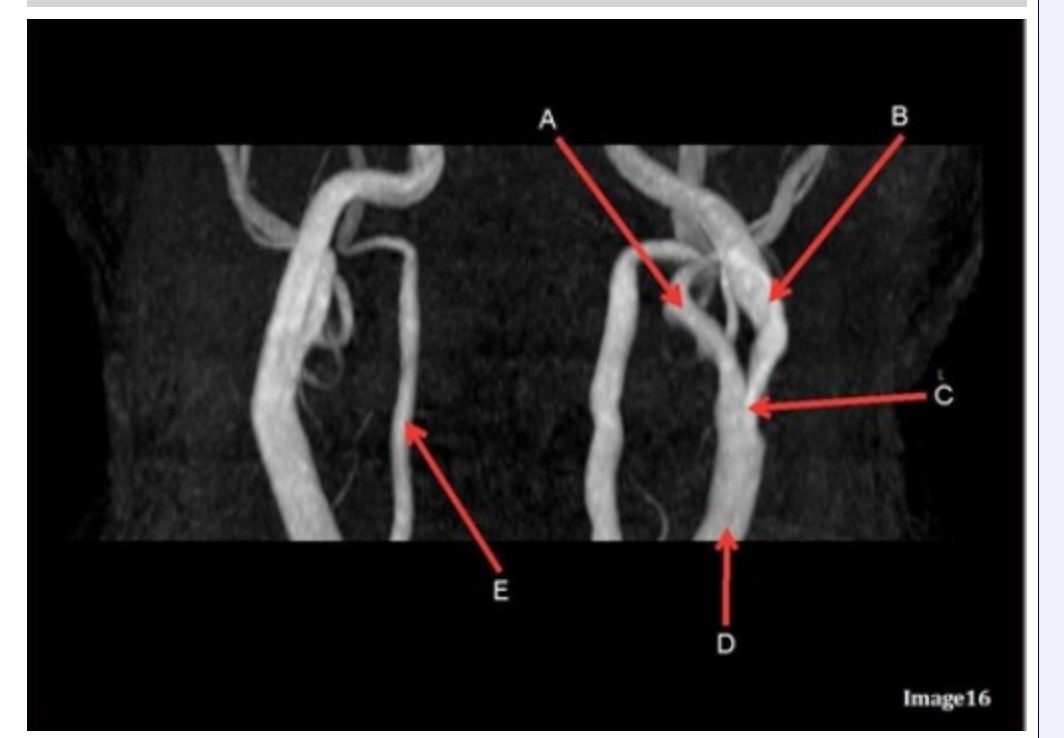

Letter B in Image 16 is pointing to:

A. Internal carotid artery

B. External carotid artery

C. Vertebral artery

D. Common carotid artery

E. Common carotid bifurcation

Letter E in Image 16 is responsible for blood supply to the:

A. Anterior brain

B. Posterior brain

C. Face

D. Upper extremities

Letter D in Image 16 is pointing to:

A. Internal carotid artery

B. External carotid artery

C. Vertebral artery

D. Common carotid artery

E. Common carotid bifurcation

Image 16 is an example of what type of MR image?

A. MR spectroscopy

B. MRA Circle of Willis

C. MRV intracranial circulation

D. MRA extracranial circulation

E. MRA intracranial circulation

Letter B in Image 16 is responsible for blood supply to the:

A. Anterior brain

B. Posterior brain

C. Face

D. Upper extremities

Letter E in Image 16 is pointing to:

A. Internal carotid artery

B. External carotid artery

C. Vertebral artery

D. Common carotid artery

Letter C in Image 16 is pointing to:

A. Internal carotid artery

B. External carotid artery

C. Vertebral artery

D. Common carotid artery

E. Common carotid bifurcation

Letter A in Image 16 is pointing to:

A. Internal carotid artery

B. External carotid artery

C. Vertebral artery

D. Common carotid artery

E. Common carotid bifurcation

Which arteries join together to form the basilar artery?

A. Vertebral arteries

B. External carotids

C. Internal carotids

D. Iliacs

E. None of the above

Letter A in Image 16 is responsible for blood supply to the:

A. Anterior brain

B. Posterior brain

C. Face

D. Upper extremities